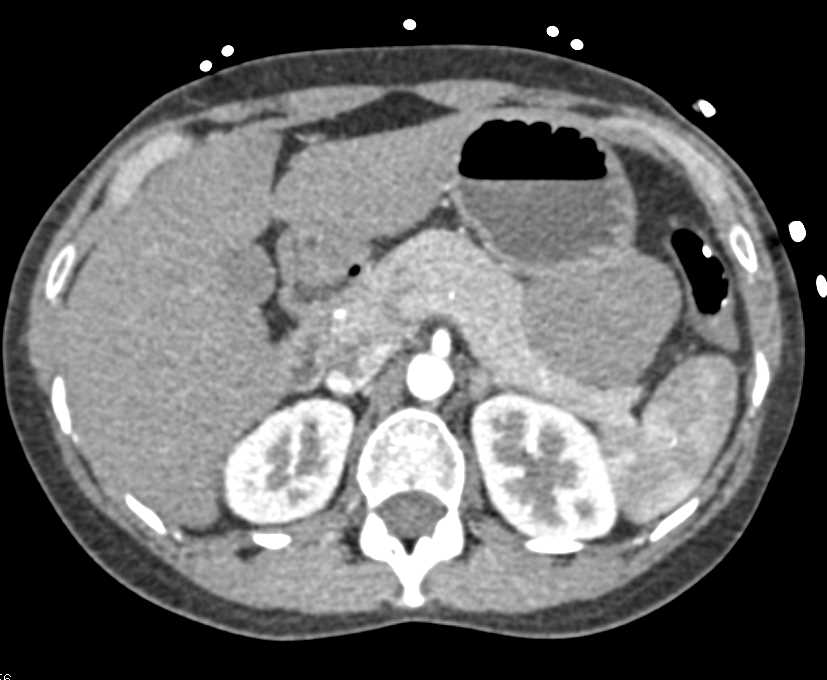

Neuroendocrine Tumor Pancreas